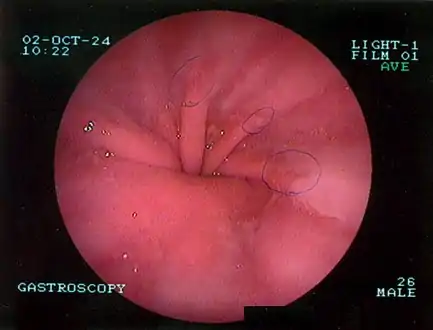

The most common risk factors are obesity and older age.[1] Other risk factors include major trauma, scoliosis, and certain types of surgery.[1] There are two main types: sliding hernia, in which the body of the stomach moves up; and paraesophageal hernia, in which an abdominal organ moves beside the esophagus.[1] The diagnosis may be confirmed with endoscopy or medical imaging.[1] Endoscopy is typically only required when concerning symptoms are present, symptoms are resistant to treatment, or the person is over 50 years of age.[1]

The diagnosis of a hiatal hernia is typically made through an upper GI series, endoscopy, high resolution manometry, esophageal pH monitoring, and computed tomography (CT). Barium swallow as in upper GI series allows the size, location, stricture, stenosis of oesophagus to be seen. Besides, it can also evaluate the oesophageal movements. Endoscopy can analyse the esophageal internal surface for erosions, ulcers, and tumours. Meanwhile, manometry can determine the integrity of esophageal movements, and the presence of esophageal achalasia. pH testings allows the quantitative analysis of acid reflux episodes. CT scan is useful in diagnosing complications of hiatal hernia such as gastric volvulus, perforation, pneumoperitoneum, and pneumomediastinum.[8]